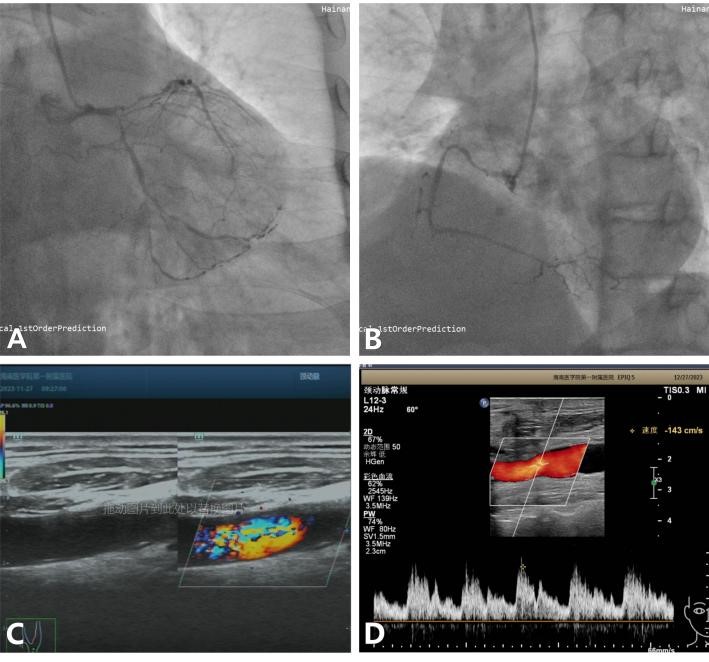

手术过程中,医生们首先通过颈部切口,小心翼翼地剥除了崔老伯颈动脉内的粥样斑块,并用心包片加宽缝合了切开的颈动脉管壁,接着,他们又在心脏跳动的情况下,用左乳内动脉和大隐静脉为崔老伯的心脏搭建了3根新的血管通道,以改善心肌的血液供应。整个手术历时4小时,顺利完成。

术后,崔老伯在心外科监护病房接受了密切的观察和护理。虽然他的肺部功能因多年吸烟和双肺肺大泡而恢复较慢,但在医护人员的精心照料下,他最终成功拔除了气管插管,并逐渐康复。心脏复查结果显示一切正常,颈动脉超声也显示左颈总动脉血流已恢复正常。最终,崔老伯痊愈出院,重新开始了他的生活。